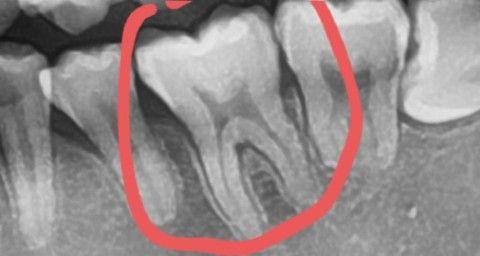

어금니 인레이 해야된다고하는데요 선생님들께서 보시기에 어떤가요?

치과의사님이 왼쪽 아래 어금니 빨간 동그라미 치아

인레이 해야된다고하시네요...

충치가 있긴하나요? 과잉진료인가요'''?

해당 사진은 파노라마입니다. 사진 상으로는 정확히 치아의 교합면 쪽의 상태를 판단하기 힘듭니다. 즉 정확히 인레이 등에 대한 치료를 판단하기 위해서는 씹는 면에 대한 임상 사진도 같이 있어야 합니다. 해당 사진만으로는 정확한 판단이 어렵습니다.

치아 사이에 충치가 잇는경우 인레이치료를 많이 합니다. 레진으로 하면 좋지만 치아 사이레진은 쉽지 않아서 추후에 문제가 생길수도 잇어서 요즘은 인레이로 많이 합니다.

인접면에 충치가 있는 경우에는 레진으로 메꿨을 경우에 경기 부위가 깨끗하게 만들어지지 않는 경우가 있습니다.

그래서 인접면 충치가 있는 경우에는 주로 인레이 치료를 많이 하게 됩니다.